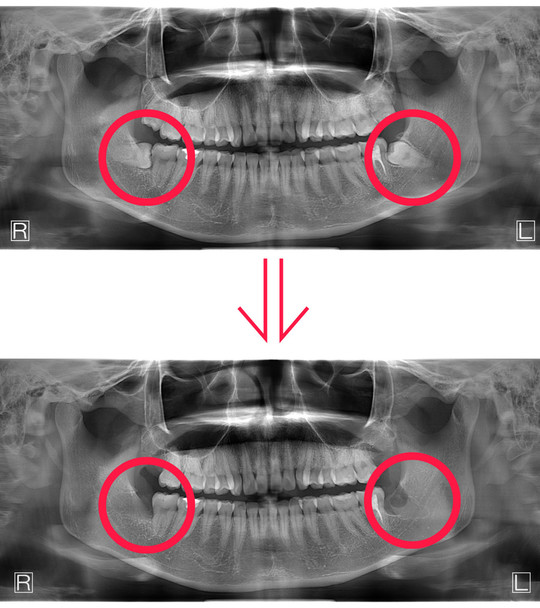

教育用のデンタルモデル、上下の歯列が詳細に再現されています。デンタルスチーマー ロコモ LOCOMO 歯科 ほぼ未使用。.:*・゜新品未使用☆。歯科インプラント補綴用器具 新品未使用。NISSIN 口腔外科用顎模型 P15-OOP.1 定価は税込36300円です。名前が書いてあるので、神経質な方はお控え下さい。☆。.:*・゜ ReFa リファ クリア。#歯科#口腔外科#実習